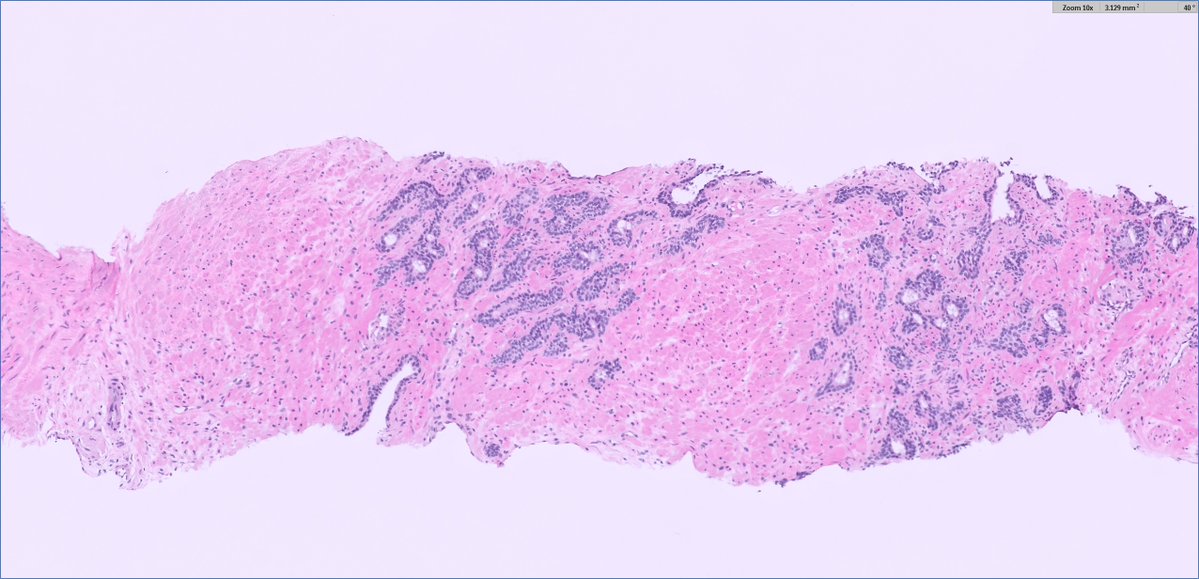

#GUpath #beautyinb9 mimic of prostate cancer on bx: 🔬basal cell hyperplasia